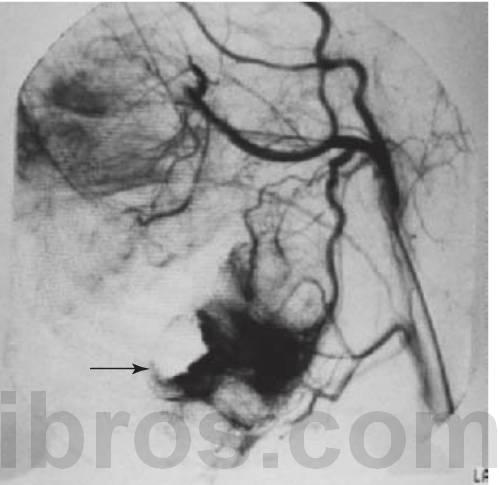

- Lesiones de mucho flujo: arteriales con fístulas arteriovenosas (fig. 8.11), que se presentan con dientes móviles y, en ocasiones, dolorosos así como pulsos palpables y auscultables, encías sangrantes y afectación ósea.

- Se precisa la realización de una angiografía de sustracción digital (fig. 8.11B) para establecer el diagnóstico definitivo de los vasos nutricios y la distribución de la lesión.

- Como ayuda al diagnóstico, puede realizarse una angiografía de resonancia magnética, pero la angiografía de sustracción digital presenta como ventaja que permite la embolización al mismo tiempo.